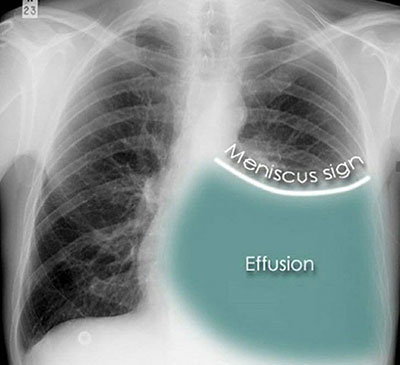

Approximate pleural effusion volume on chest X-ray (upright PA) — rough reference (Written February 23, 2026)